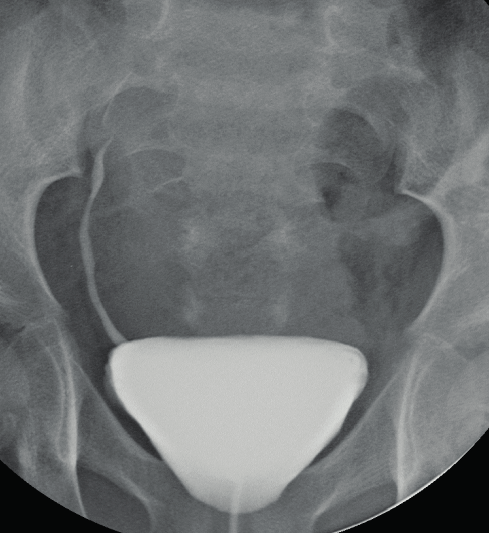

Mictie cystogram

In het algemeen wordt dit onderzoek, wanneer het gedaan wordt om een urethrastrictuur in beeld te brengen, alleen verricht bij mannen die al een suprapubische catheter (buikcatheter) hebben.

Het doel van dit onderzoek is het functioneren van de blaas zichtbaar te maken met behulp van röntgenstralen. U krijgt tijdens het onderzoek via een katheter contrastmiddel toegediend. Zonder dit contrastmiddel is de blaas niet zichtbaar.

U neemt plaats op de röntgentafel. Vervolgens laat de radioloog via de buikcatheter jodiumhoudende vloeistof (contrastmiddel) in de blaas lopen.

Zonder dit contrastmiddel is de blaas niet zichtbaar. Het contrastmiddel loopt in de blaas tot u aandrang tot plassen heeft. U geeft zelf aan wat de grens is. De radioloog zal aan u vragen of u uit wilt plassen terwijl u tussen het röntgenapparaat staat. U krijgt hiervoor een speciaal bakje of fles.

Tijdens het uit plassen maakt de radioloog röntgenfoto’s van de blaas en urinewegen. Het onderzoek is klaar als de blaas leeg is. In de meeste gevallen duurt het onderzoek ongeveer 30 minuten. De radioloog beoordeelt de beelden na afloop van het onderzoek. Hij maakt een verslag en stuurt dit naar uw uroloog. Uw uroloog bespreekt met u de definitieve uitslag.